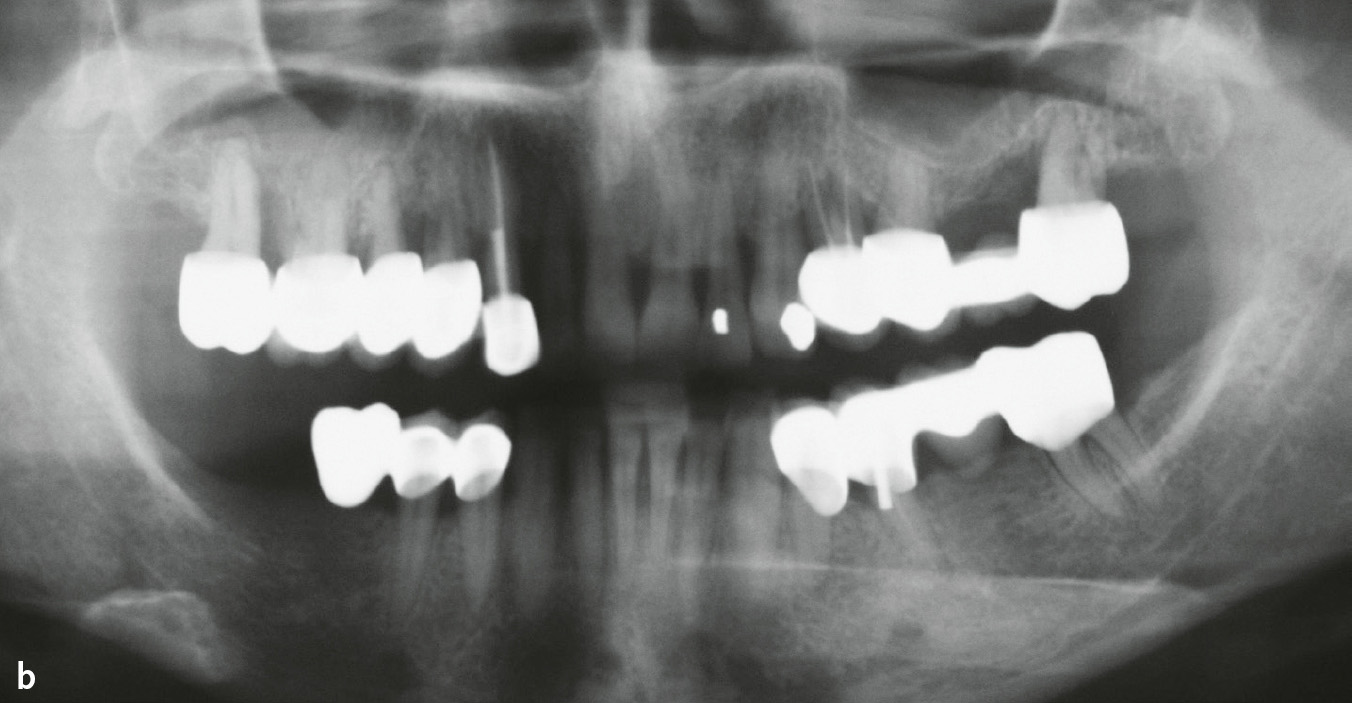

Abb. 6a und b Mann im Alter von 60 bzw. 61 Jahren, starker Raucher, Parodontitis, generalisiertes Stadium IV, Grad C; 1962 bis 1995 20 Zigaretten/Tag, seit 1995 10 Zigaretten/Tag (etwa 44 Packungsjahre): a) Klinische Ansicht im Alter von 61 Jahren; b) Panoramaschichtaufnahme im Alter von 60 Jahren.

Abb. 7a und b Lokale Parodontitis-Risikofaktoren: a) Zahn 36 nach Tunnelierung mit breitem und weit in den Furkationsfornix reichenden bukkalen Schmelzsporn; b) Panoramaschichtaufnahme einer Frau im Alter von 35 Jahren (1995): Parodontitis, generalisiert Stadium III, Grad C. Der Zahnersatz mit zum Teil stark überhängenden Kronenrändern wurde im Jahr 1994 eingegliedert.